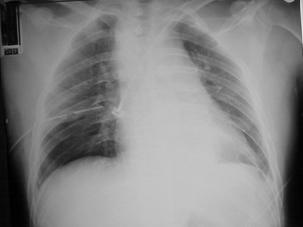

TRAUMATISME TORACICE

Pneumotorace sufocant bilateral Pneumotorace sufocant stang

Pneumotorace

sufocant stang Pneumotorace

sufocant drept Pneumotorace

sufocant drept